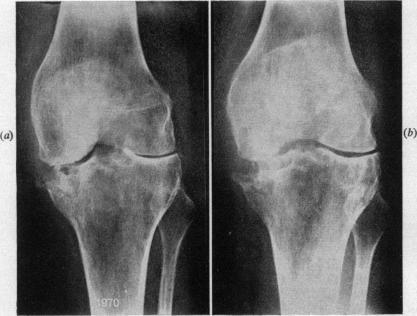

Surgical treatment of Still's disease.

Ann R Coll Surg Engl. 1973 Nov;53(5):288-99.